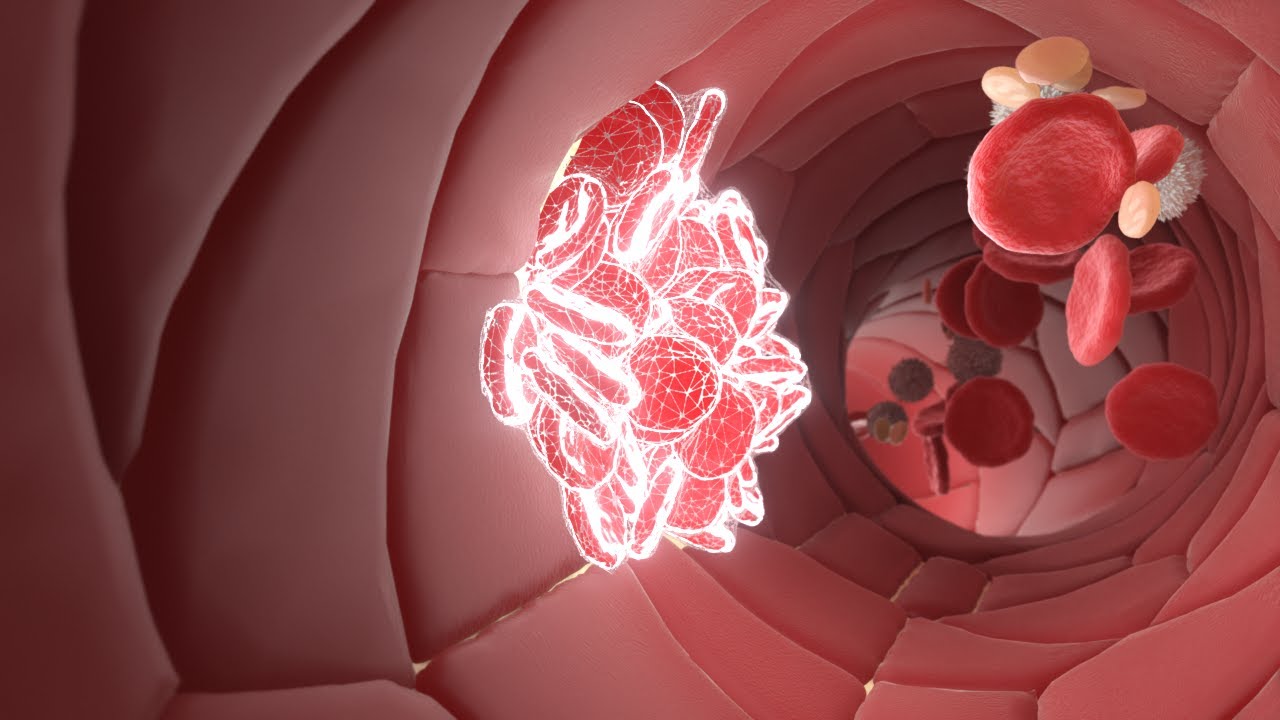

Hemostaz